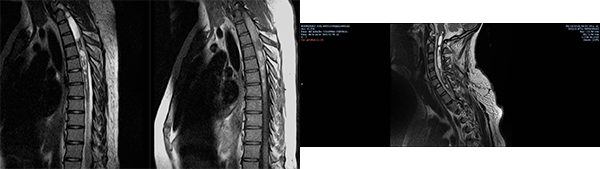

Se registraron dos reoperaciones ( casos 3 y 5 ). En el Caso 5 el paciente experimentó un empiema en el lecho quirúrgico y requirió retiro de la laminoplastía, lavado del foco infeccioso y tratamiento antibiótico por tres semanas, este paciente con Grado 3 en la escala de McCormick se mantuvo con Grado V de la misma escala de manera irreversible luego de un año de la cirugía. El caso 3 se trató de un tumor del cono medular diagnosticado inicialmente como Ependimoma Mixopapilar de la Cola de Caballo (Grado I OMS) en el que observó un residuo sobre la cara anterior medular en una IRM de control (Figuras 1 y 2). La reexploración evidenció la ubicación intramedular de la lesión y la revisión anatomopatológica definitiva concluyó que se trataba de un Ependimoma (Grado II OMS).

Figura 1: Caso 3. Ependimoma Dorsolumbar. Residuo cara anterior